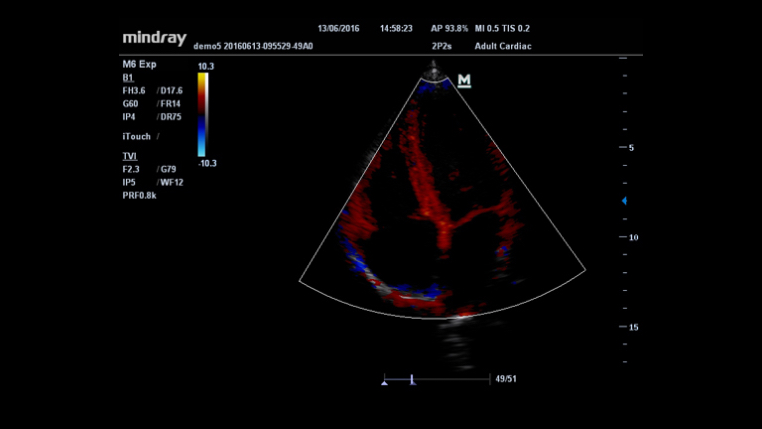

HR Flow?

iTouch? (automatyczna optymalizacja obrazu)

Funkcja ta pozwala uzyska? natychmiastow? automatyczn? optymalizacj? obrazu w trybach B, Kolorowego Dopplera i PW (Spektralnego Dopplera Fali Pulsacyjnej) poprzez naci?ni?cie jednego klawisza.